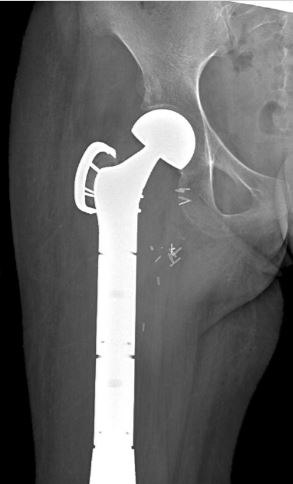

This is an x-ray of a patient after the surgical placement of the prosthesis and removal of upper femur.